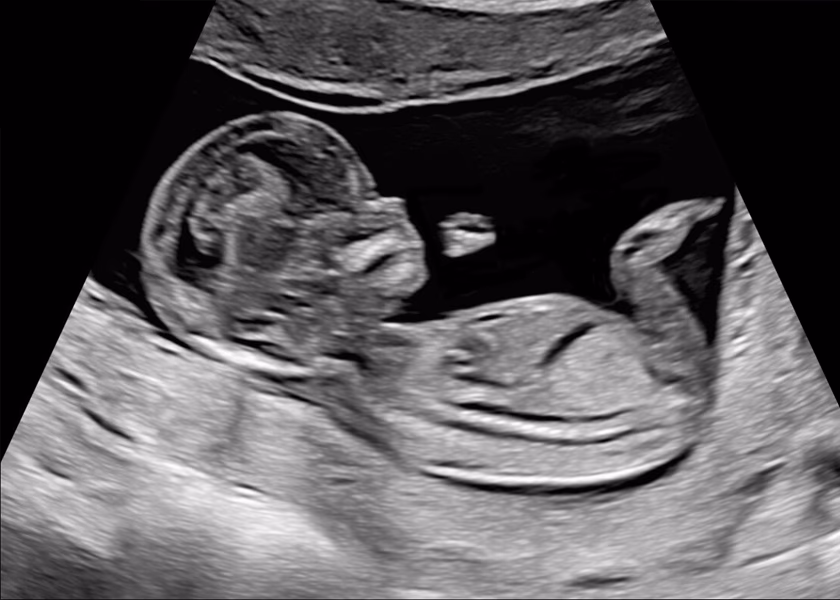

Vid ultraljud i första trimestern dateras graviditeten och du får ett beräknat förlossningsdatum. Fostret är nu cirka 6-7 cm mellan huvud och rumpa (CRL, Coronary Rump Lenght).

Vi kontrollerar antal foster, hjärtaktivitet och fostervattenmängd. Fostrets anatomi granskas noggrant för att upptäcka eventuella avvikelser, och moderkakans läge bedöms. Undersökningen görs via magen.

Rutinultraljudet görs via magen i graviditetsvecka 19 för att gå igenom anatomin på fostret enligt en checklista, titta var moderkakan sitter, kontrollerar hjärtaktivitet, fosterrörelser samt mängden fostervatten. Har du inte gjort något tidigare ultraljud sätts ett beräknat förlossningsdatum i samband med rutinultraljudet och vi tittar på hur många foster det är i magen.

Vid det här ultraljudet är fostret cirka 20 cm och vi kan också se vad det är för kön, om du vill veta det.